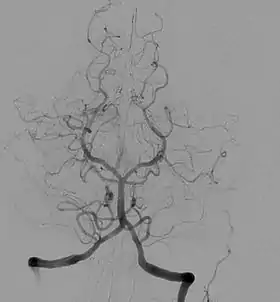

![]() Angiogram showing a transverse projection of the vertebrobasilar and posterior cerebral circulation. | |